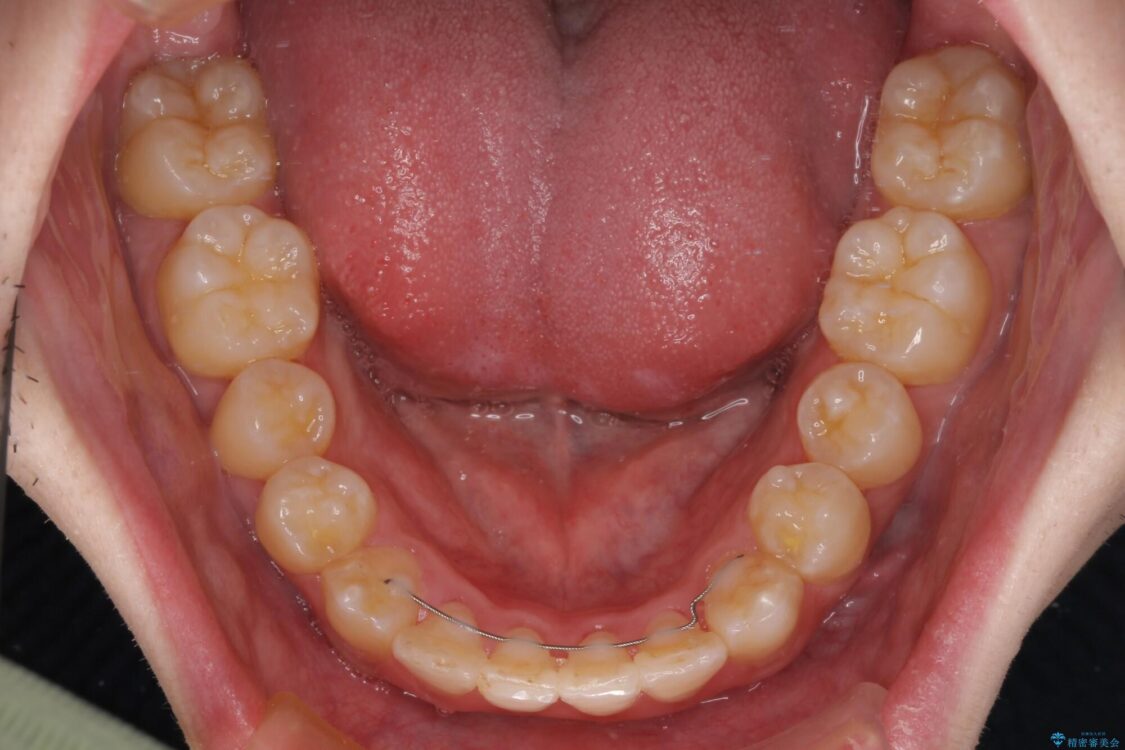

シザーズバイトは強く咬合する奥歯を移動させるため、多くの場合においてワイヤー矯正の装置のみでは改善が困難となります。

奥歯の咬み合わせ改善は治療初期からしっかりとアプローチする必要があるため、補助装置を積極的に利用します。

治療後